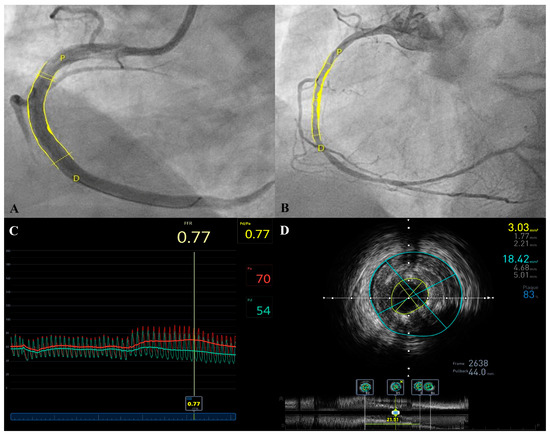

3.2. Clinical and Radiological Outcome